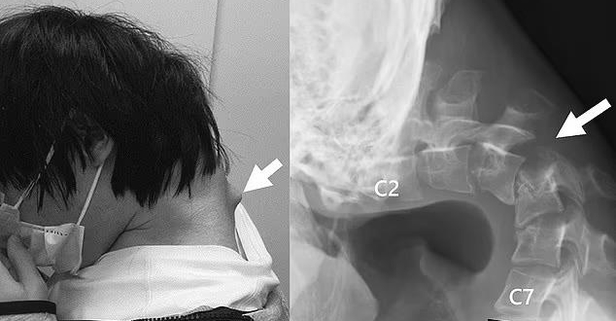

Japonya’da bir gencin telefona bakmaktan boynu yamuldu. Düşük Kafa Sendromu teşhisi konulan 25 yaşındaki gencin boynuna operasyonla vida ve metal çubuklar yerleştirildi. Dünyayı şoke eden vakanın ardından uzmanlardan telefon ve tablet uyarısı geldi.

25 yaşındaki gence Düşük Kafa Sendromu teşhisi konuldu. Gencin sürekli telefona baktığı ve başını kaldırmadığı için bu hale geldiği belirtildi.

Elle müdahale ve atelin yetersiz kalmasının ardından doktorlar cerrahi operasyona karar verdi.

Hasarlı omur ve dokuların çıkarıldığı operasyonda gencin boynuna vida ve metal çubuklar yerleştirildi. Ameliyattan ancak altı ay sonra hastanın başını kaldırmaya başladığı, bir yıl içinde hareket kabiliyeti kazandığı belirtildi.